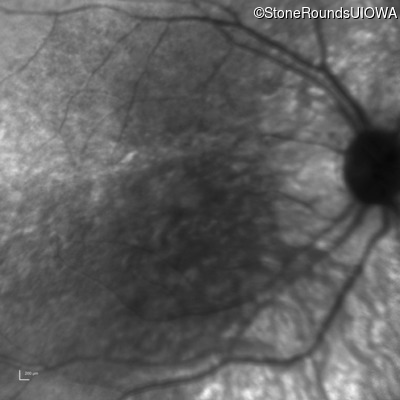

Infrared Fundus Photograph - Right - 5/200 sc

Exemplar

Infrared Fundus Photograph - Right - 10/700 sc